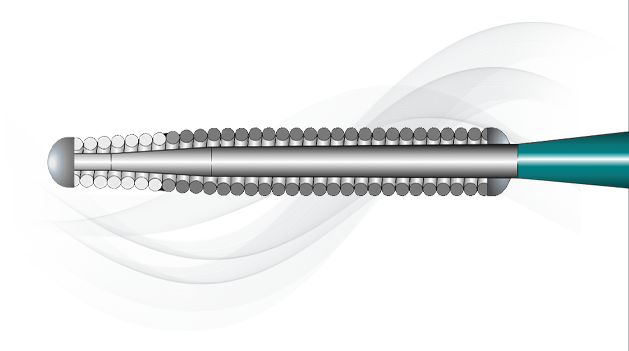

Micro EMTTM Technology

MICRO EMT exactly matches the taper of the core and coil, allowing for a lower profile and a more flexible core, leaving almost no room for the core to move within the coil, resulting in 1:1 torque.

- Entry: The smallest tip on the market (0.008”) and the long taper (6 cm) facilitate easy lesion entry in even the most complex lesions.

- Maneuverability: A flexible distal shaft enables excellent intraluminal navigation in complex lesions, with minimal perforation risk.

- Torque: With exactly matched tapers, the core and coil move as one, eliminating whip and empowering precise steerability.